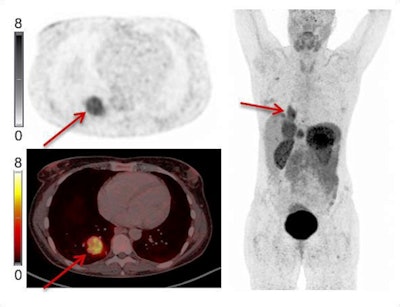

Example of Ga-68 NODAGA-E[c(RGDyK)]2 PET/CT. Transaxial PET and fused PET/CT and maximum intensity projection with color bars (unit: SUV). Patient with lung neuroendocrine tumor grade 2 (Ki67 15%) with liver and bone metastases. Arrow at primary tumor. Image courtesy of the Journal of Nuclear Medicine.The researchers found a significant association between radiotracer uptake and both progression-free survival and overall survival. Patients with an SUVmax above 5.25 had a hazard ratio (HR) of 2.11 for PFS and 6.95 for OS, the researchers wrote.